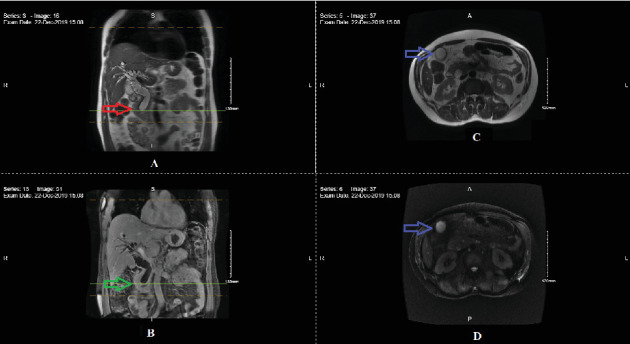

转移性壶腹癌(AC)几乎总是预后不良。我们报告了一个值得注意的病例,一位69岁的男性IV期胰胆型AC患者在经过45个月的姑息性改良FOLFIRINOX化疗(5-氟尿嘧啶、奥沙利铂、亚叶酸钙、伊立替康)后完全缓解。这一意想不到的结果挑战了对晚期AC自然史的传统理解。此外,分子分析显示,在编码各种脱氧核糖核酸(DNA)修复途径的酶的POLD1和RAD50基因中,存在致病性PALB2突变以及未知意义的变异。这些发现提出了它们对治疗反应和预后的潜在影响的问题。该病例强调需要进一步研究分子改变和个性化方法在晚期AC治疗中的作用。

Metastatic ampullary carcinoma (AC) almost always carries a poor prognosis. We present a remarkable case of a 69-year-old male with Stage IV pancreaticobiliary-type AC who achieved a complete remission after 45 months of palliative modified FOLFIRINOX chemotherapy (5-fluorouracil, oxaliplatin, leucovorin, irinotecan). This unexpected outcome challenges the conventional understanding of the natural history of advanced AC. Furthermore, molecular analysis revealed a pathogenic PALB2 mutation, along with variants of unknown significance in the POLD1 and RAD50 genes, coding for enzymes involved in various deoxyribonucleic acid (DNA) repair pathways. These findings raise questions about their potential influence on treatment response and prognosis. This case underscores the need for further investigation into the role of molecular alterations and personalized approaches in managing advanced AC.